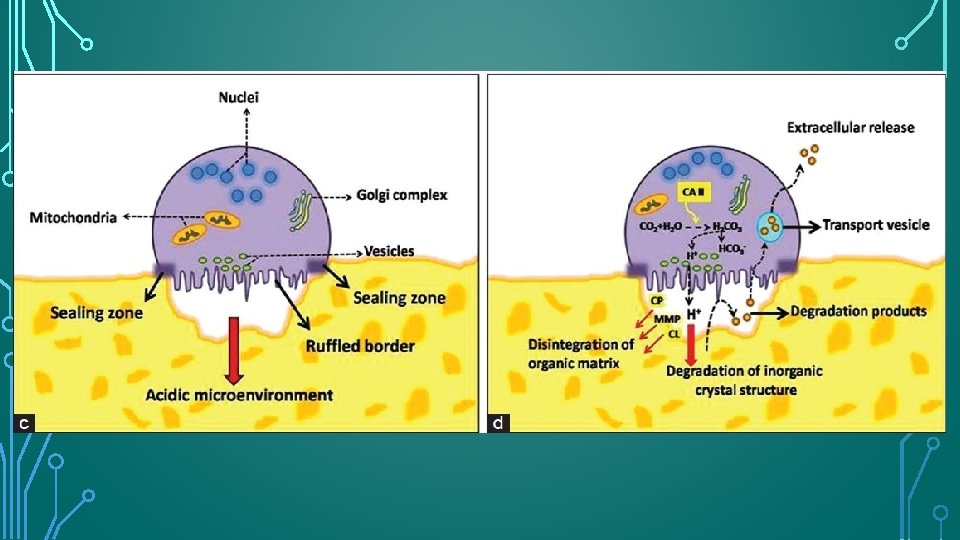

OSTEOCLAST FUNCTION • Osteoclasts are recruited to the site of. injury or irritation by the release of many proinflammatory cytokines. To perform their function, osteoclasts must attach themselves to the bone surface. On contact with mineralized extracellular matrices, osteoclast produces an organelle-free zone of sealing cytoplasm (clear zone) to achieve intimate contact with the hard tissue surface. • The clear zone surrounds a series of fingerlike projections (podosomes) of cell membrane, known as the ruffled border, beneath which bone resorption occurs. The resorptive area within the clear zone, therefore, is isolated from the extracellular environment, creating an acidic microenvironment for the resorption of hard tissues

ODONTOCLAST FUNCTION • Odontoclasts differ from osteoclasts in that they are smaller, have fewer nuclei, and have smaller sealing zones. • Odontoclasts and osteoclasts are functionally similar, have similar enzymatic properties, show similar cytologic features, and create resorption depressions, termed Howship lacunae.

• 119 • Wesselink et al. demonstrated that odontoclasts can simultaneously have two areas of ruffle border, which can resorb bone and hard dental tissue concurrently. • Based on this evidence, Jones and Boyd and Pierce have stated that odontoclasts and osteoclasts are effectively the same cell type, differing only in their respective substrata.

PROPERTY OF CLASTIC CELLS Osteoclasts and odontoclasts do not adhere to non-mineralized collagen matrices.